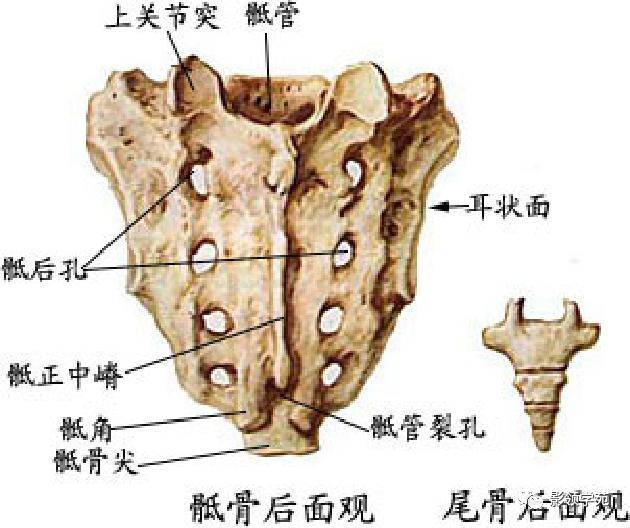

骨骼系统

骨骼系统